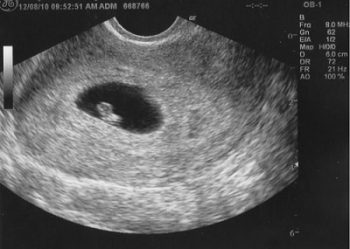

Tiếp nối sự phát triển của thai nhi ở tuần 4, thai 5 tuần tuổi là giai đoạn đầu của thai kỳ, tính từ ngày đầu tiên của kỳ kinh cuối cùng. Lúc này, phôi thai chỉ dài khoảng 1,5–2mm, Thai nhi 5 tuần tuổi có kích thước rất nhỏ, hình dạng riêng biệt của thai nhi đã được hình thành nhưng chưa có hình dạng của con người mà giống như một nòng nọc con có đuôi.

Thông thường, ở tuần thai thứ 5, phôi thai đã di chuyển vào tử cung và làm tổ ổn định trong lớp niêm mạc tử cung.

Kích thước thai khá nhỏ, với chiều dài khoảng 1,5–2mm, do đó có thể phá thai được.